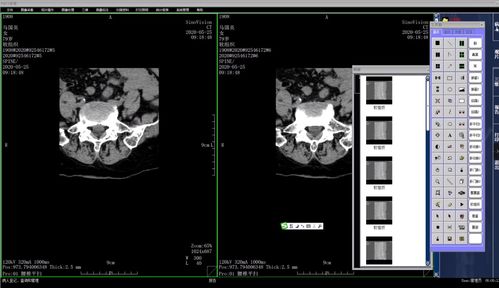

1. 骨折诊断

CT医学影像系统可以清晰地显示骨骼的形态和结构,对于骨折的诊断具有很高的准确性。